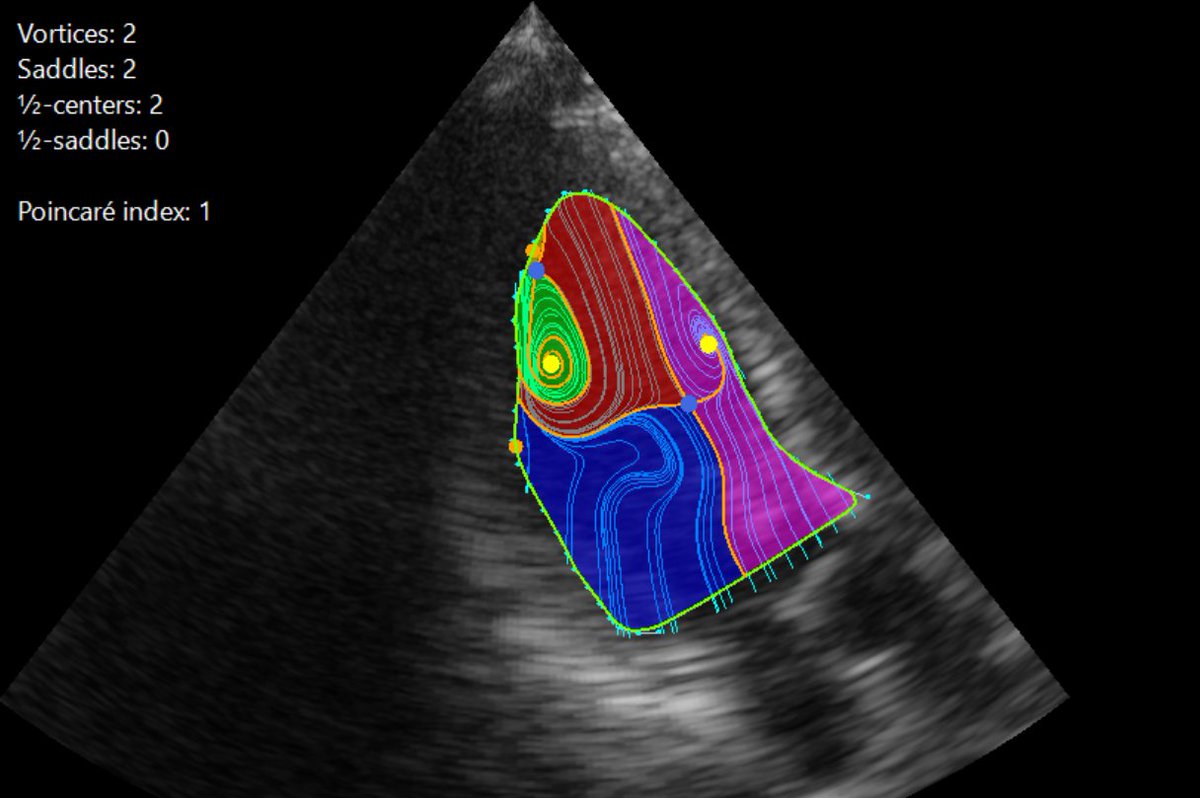

㊗️板谷先生 左室渦流🌊 #Topological 理論 🫀短時間範囲で収縮弛緩繰り返すため位相分類理論で想定の滑り境界条件満たしていない👉n-bundled ss-saddle縮退特異点導入👉🌊構造トポロジカル渦構造識別に成功🎉非効率血流パターン #Energyloss 可視化成功🎉🎉🎉 キャ~😆

渦の中心を何個発見できますか? 心臓内の『渦血流』を同定する理論を世界に先駆けて構築:心血流の渦のパターンを文字化し、早期に心不全を発見する可能性 jst.go.jp/pr/announce/20… #心臓は血流で診断する時代へ #血流解析 #VFM #カーディオフローデザイン #心エコー #心不全 #早期発見

CFD_Inc's tweet image. 渦の中心を何個発見できますか?

心臓内の『渦血流』を同定する理論を世界に先駆けて構築:心血流の渦のパターンを文字化し、早期に心不全を発見する可能性